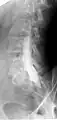

Myelogram showing arachnoiditis in the lumbar spine.